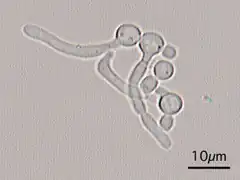

This "hyphal" denomination is due to Hwp1 appearing exclusively on the surface of a projection called hyphae that emerges from the surface of this fungus.

Candida Albicans Yeast forms (round-to-oval) -

Candida Albicans Hyphal forms (filamentous projections called hyphaes emerging from round-to-oval forms)